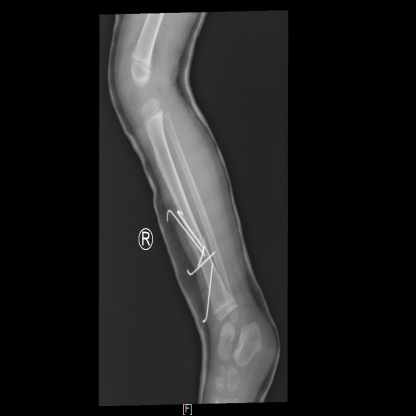

5枚克氏针固定

术中右小腿持续牵引后,手法复位及克氏针翘拨复位,透视下见骨折复位良好,用5枚2.0mm钛克氏针固定骨折,再次透视,调整克氏针位置,见骨折断端对位对线好,右膝、右踝关节伸屈活动可。克氏针尾弯曲,剪短后留于皮外,碘伏无菌敷料包扎,足背动脉搏动有力,行右下肢功能位管型石膏外固定,观察见末梢血运良好。

胫腓骨骨折常见的诊疗方案采用髓内针固定,但该患儿存在胫骨纵向劈裂骨折,涉及髓腔,髓内针固定时可能因占位导致骨折间隙增大,骨折片位移错位产生畸形愈合。采用克氏针治疗,骨折固定效果确切,表面皮肤无切口,手术创伤小,术后恢复快,满足患儿及家长对皮肤美观的要求。而且克氏针固定与钢板及外固定支架相比,费用低廉,减轻患儿家庭经济负担。

术后给予患儿儿童骨折优质护理,止血及消肿治疗,抬高患肢,注意观察患肢末梢血运。复查X线示:右侧胫腓骨可见外固定影,右胫骨下段可见金属内固定,断端对位对线可,周围未见明确骨痂形成。小曹病情平稳,向患儿家属交代病情及出院注意事项,现已顺利出院。